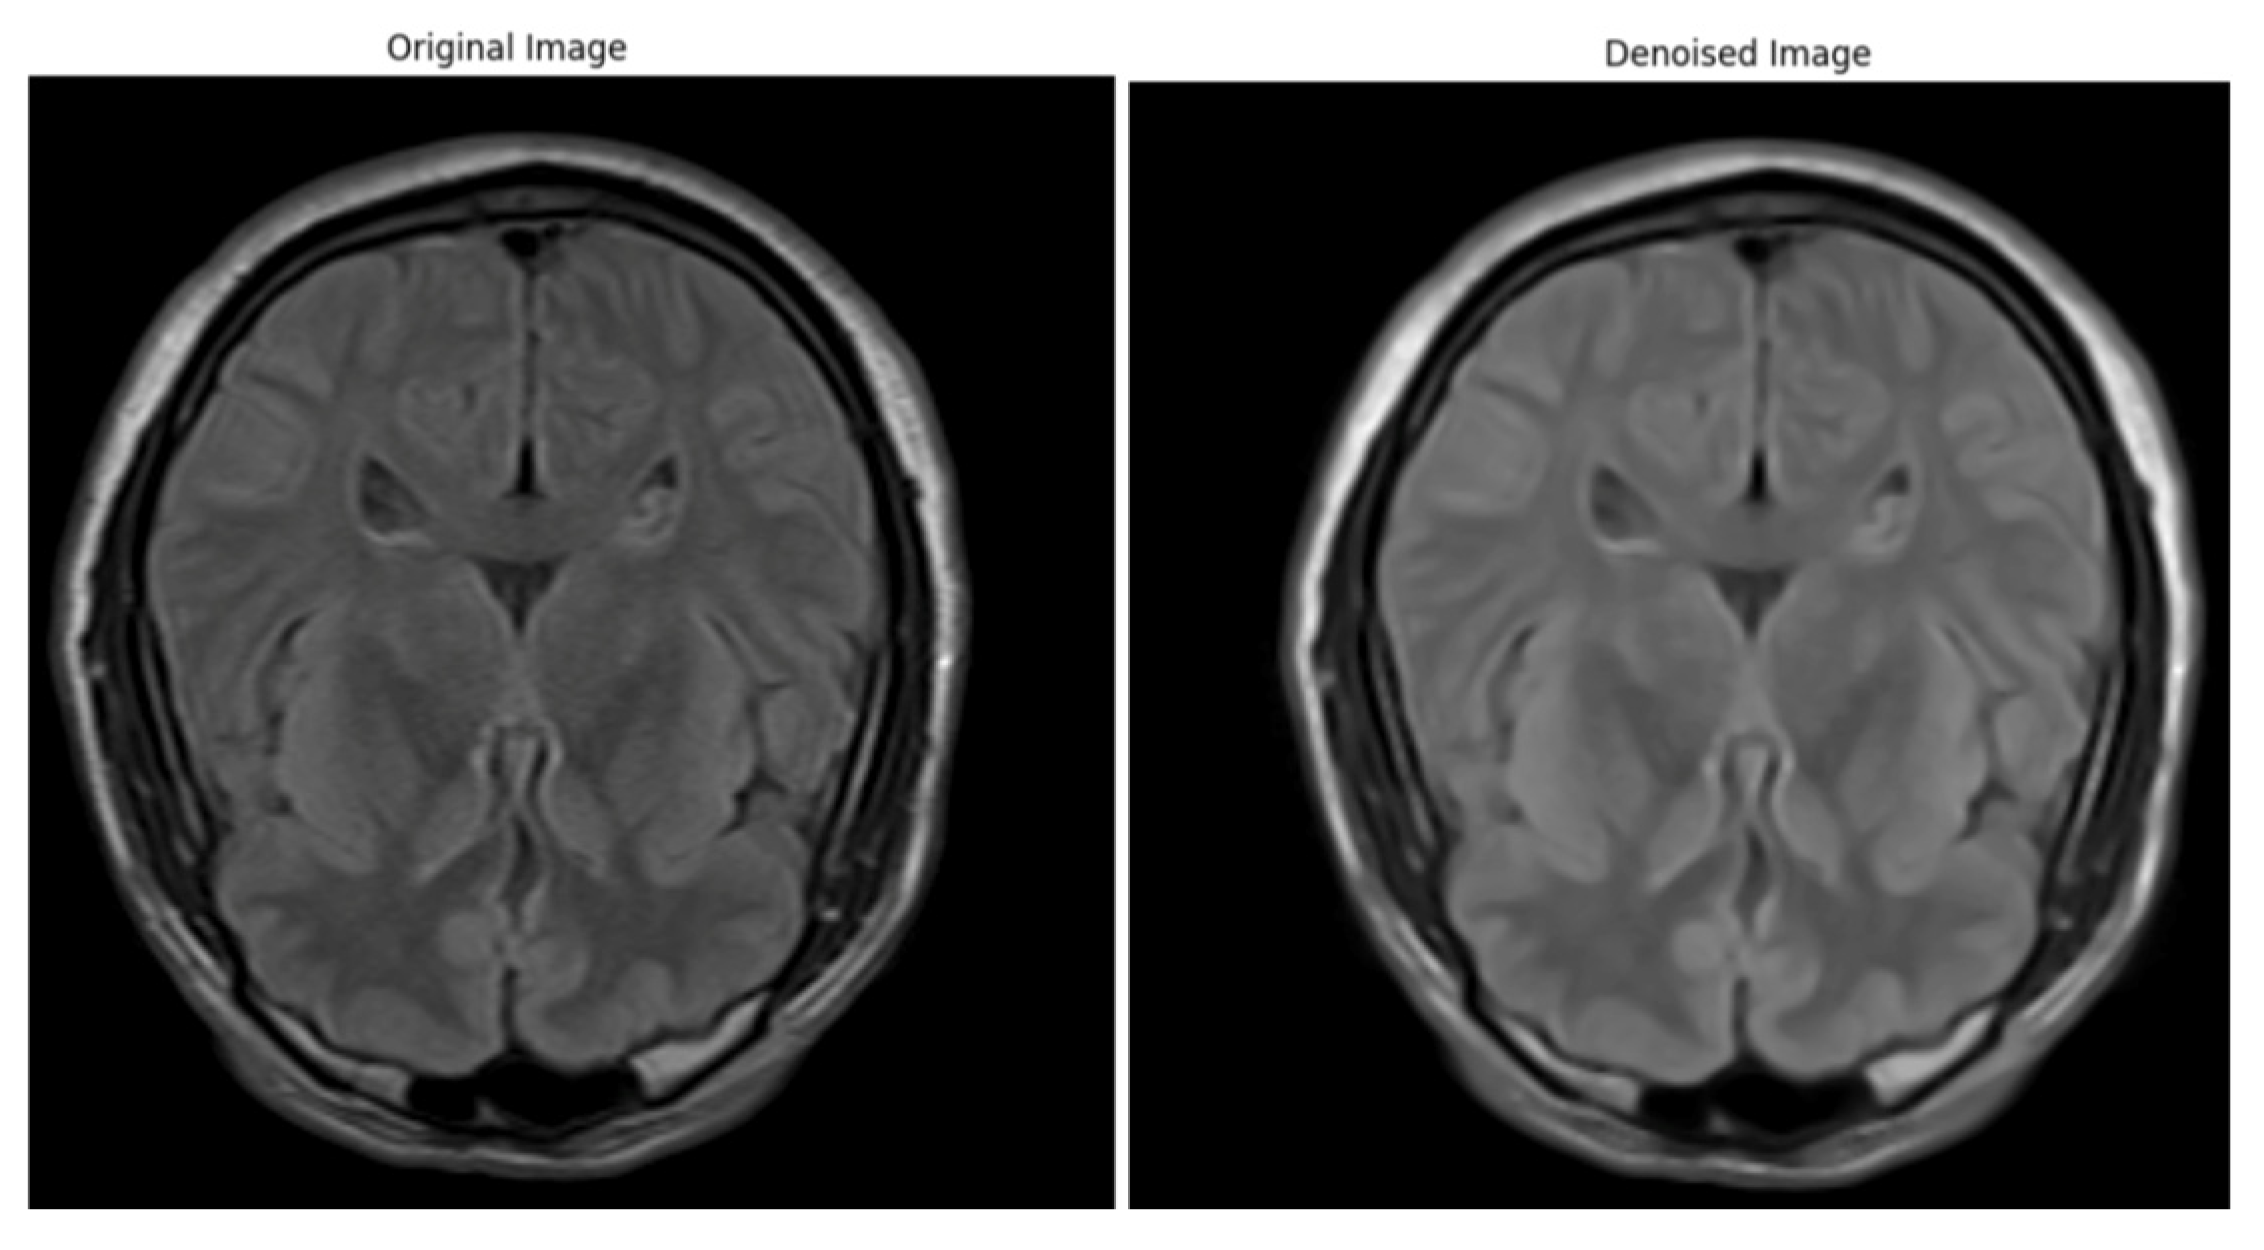

Artifacts and Noise Reduction

Bias Field Correction

Image Normalization